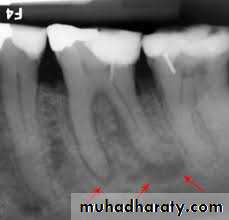

Periodontal or periapical disease → alveolar bone loss →lack of periodontal support.

Inadequate crown - root ratio.

Pulp pathosis→periapical lesion(abcess →granuloma →cyst)

(The smaller the radiographic emage, the more likely the diagnosis is granuloma is correct)

According to Lalonde:

0-1cm →70% granuloma-30% cyst.

1-2cm →40% granuloma-60% cyst.

↑2cm →100% cyst.

Tay etal demonstrated that the success of conservative endodontic therapy deminished with the increased size of the periapical lesion